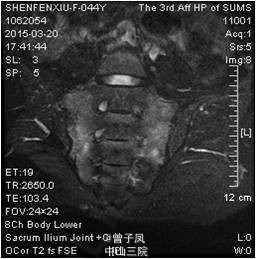

两侧斜方肌上缘中点、两侧第2肋骨与软骨交界处的外上缘、两侧肩胛棘上方近内侧缘起始部、两侧臀部外上象限、两侧大转子后方均有明显压痛。胸廓扩张度4cm,改良Schober 试验3cm,指地距45cm,枕墙距0cm,耳壁距2cm。双侧下肢4字征(+),足掌、踝部轻压痛。 我院 骨盆腰椎正位:骨盆、腰椎退行性变。足部右侧正斜位:双足骨质疏松。骶髂关节(骨盆)MR平扫+增强 :1、双侧骶髂关节所见,考虑脊柱关节炎,关节面下骨髓水肿。2、盆腔积液。 生化全套:磷0.610mmol/L,球蛋白22.100g/L,碱性磷酸酶209.000U/L。 风湿二项、C反应蛋白、ESR、结核杆菌抗体、HLA-B27、ENA谱、ANA、甲功三项、尿常规、大便常规、均未见明显异常。